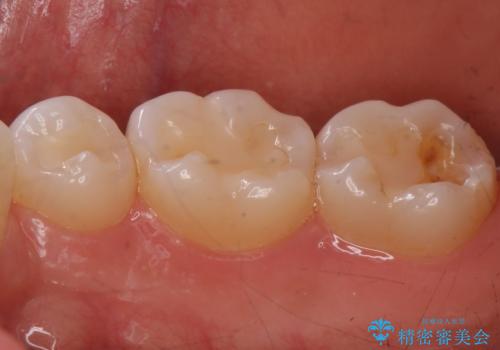

食いしばりが強い方はセラミックがまた割れる可能性があるため、予防的にナイトガードを装着することをお勧めします。

- かみ合わせや歯ぎしりが強すぎる方はセラミックが割れてしまう可能性があります